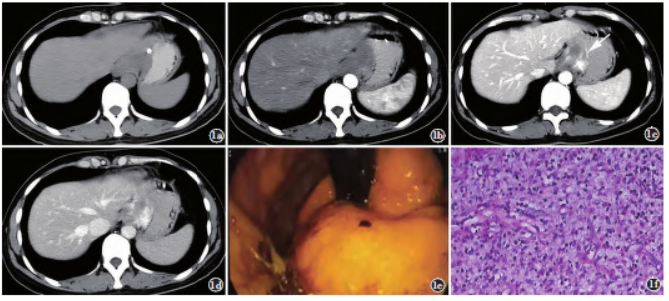

病例1,女,39岁,1年前无明显诱因出现饭后哽噎,症状反复。实验室检查无特殊。查体:全腹无压痛及反跳痛,无肌紧张,未触及肿块。上腹部CT检查提示贲门胃小弯侧黏膜下不规则肿块,浸润性生长,大小约4.2cm×2.4cm,平扫呈稍低密度,边缘见钙化,增强三期呈渐进性强化,邻近贲门及小弯侧黏膜增厚且强化明显(图1a~1d),CT诊断胃间质瘤。超声内镜示贲门部低回声病灶伴出血,性质待定(图1e)。

全麻下行胸腹腔联合近端胃大部食管下段切除术,术后大体病理示肿块切面灰白,实性,编织状;镜下示贲门隆起处黏膜腺上皮无明显异型,黏膜下层、肌层可见水肿性黏液样背景下纤维母细胞增生,慢性炎细胞浸润,并见小血管增生(图1f);免疫组化:CAM5.2(上皮+)、VI(部分+)、Des(部分+)、SMA(部分+)、CD34(部分+)、C-kit(-)、Dog-1(-)、S-100(-)、LCA(淋巴细胞灶性+)、Ki-67(2%),病理诊断:胃部炎性肌纤维母细胞瘤。患者术后随访至今,未见复发及转移灶。

图1病例1。a)上腹部CT平扫b)增强动脉期;c)静脉期;d)延迟期轴位示贲门胃小弯侧不规则肿块,浸润性生长,平扫呈稍低密度影,边缘见钙化,呈轻度渐进性强化,强化均匀;c)贲门及小弯侧黏膜增厚,且强化明显(箭);e)内镜图;f)镜下病理图(HE染色,×100)